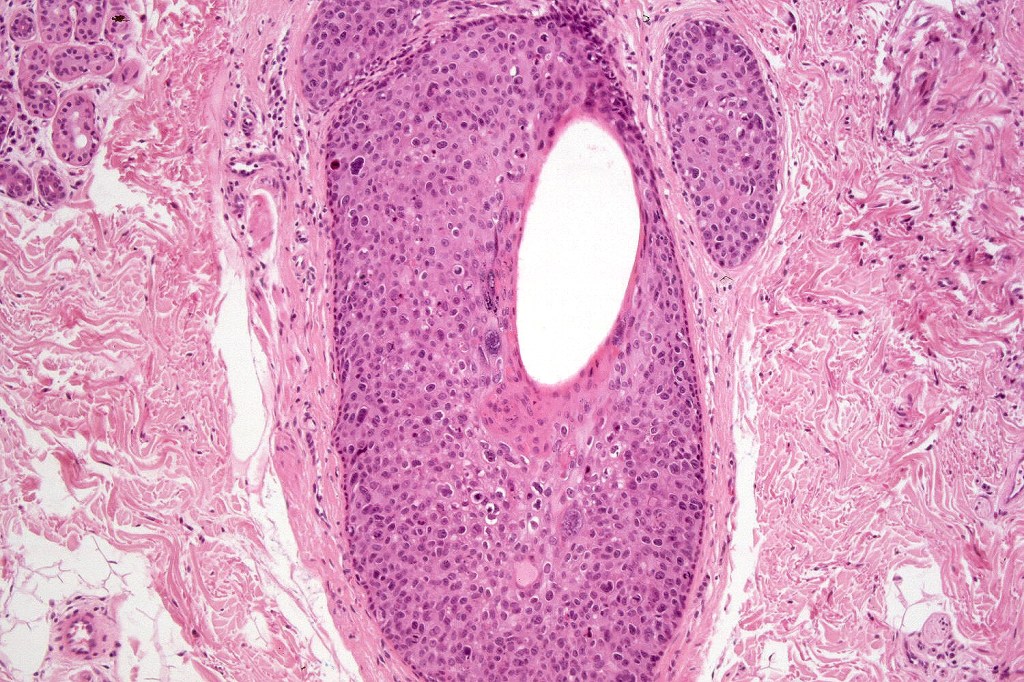

•Hyperkeratotic/hyperplastic actinic keratosis represents the prototype-alternating hyperkeratosis & parakeratosis- the former overlies the follicular & sweat duct ostia (Freudenthal funnel) while the latter overlies the interadnexal dysplastic epithelium & ranges from basal cell layer though to full thickness dysplasia (Bowenoid actinic keratosis); budding from the epidermis is a common finding; dysplastic epithelium commonly forms a mantle around the follicles and superficial sweat ducts